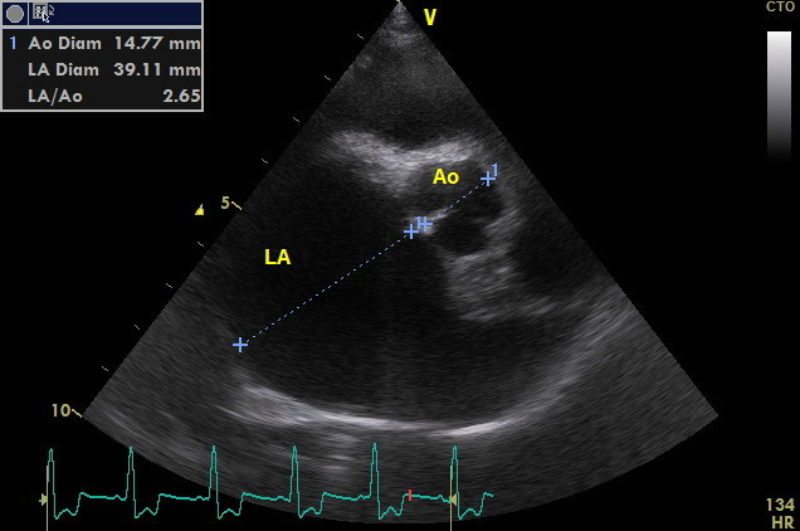

Herzultraschall

Durch die Herzultraschalluntersuchung konnte dann leider der Verdacht auf eine deutlich weiter fortgeschrittene Herzerkrankung bestätigt werden. Neben einer hochgradigen Vergrößerung der linken Herzhälfte durch die Klappeninsuffizienz ließ sich außerdem ein moderat erhöhter Druck in den Lungenarterien feststellen. Dies nennt man Pulmonale Hypertension oder Lungenhochdruck. Für eine solche Erhöhung des Blutdruckes im Lungenkreislauf gibt es unterschiedliche Ursachen. Eine davon ist ein bestehendes Lungenödem durch ein Linksherzversagen, wie es bei Alf nun offensichtlich der Fall war. Da die Diagnose nun „dekompensierte Mitralklappenendokardiose“ - oder nach der CHIEF - Klassifizierung Stadium C2 * - lautete, verordnete ich dem kleinen Hund zusätzlich zwei weitere Medikamente zur dauerhaften Herztherapie (eines zur Entwässerung und das andere zur Entlastung des Herzens durch Weitstellung der Arterien und zur Unterstützung der Pumpfunktion des Herzmuskels). Die am Morgen im Wald aufgetretene „Synkope“ ließ sich also eindeutig durch die fortgeschritten Herzerkrankung erklären.